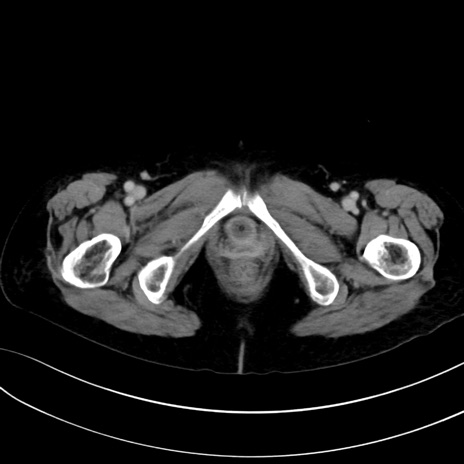

症例13 CT(横断像)1日半後